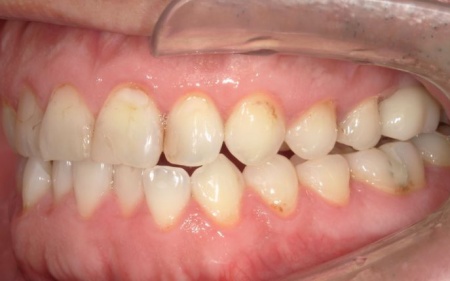

以上のことから、口腔内を全体的に治療する必要があると診断しました。

口腔内の健康状態を改善しつつ、歯磨きなどのケアをしやすくするために、以下の治療方法を提案して同意いただきました。

④上下左右の奥歯には、銀合金の古い詰め物「アマルガム」が装着されていました。今回は保険診療の範囲内で、CRと金属の詰め物「インレー」による修復を行い、全体的な噛み合わせと審美性を改善します。

最後に、古いアマルガムを除去した部分は保険診療の範囲で治療を行い、見た目や噛み合わせなどに問題がないことを確認して、治療を終了しています。